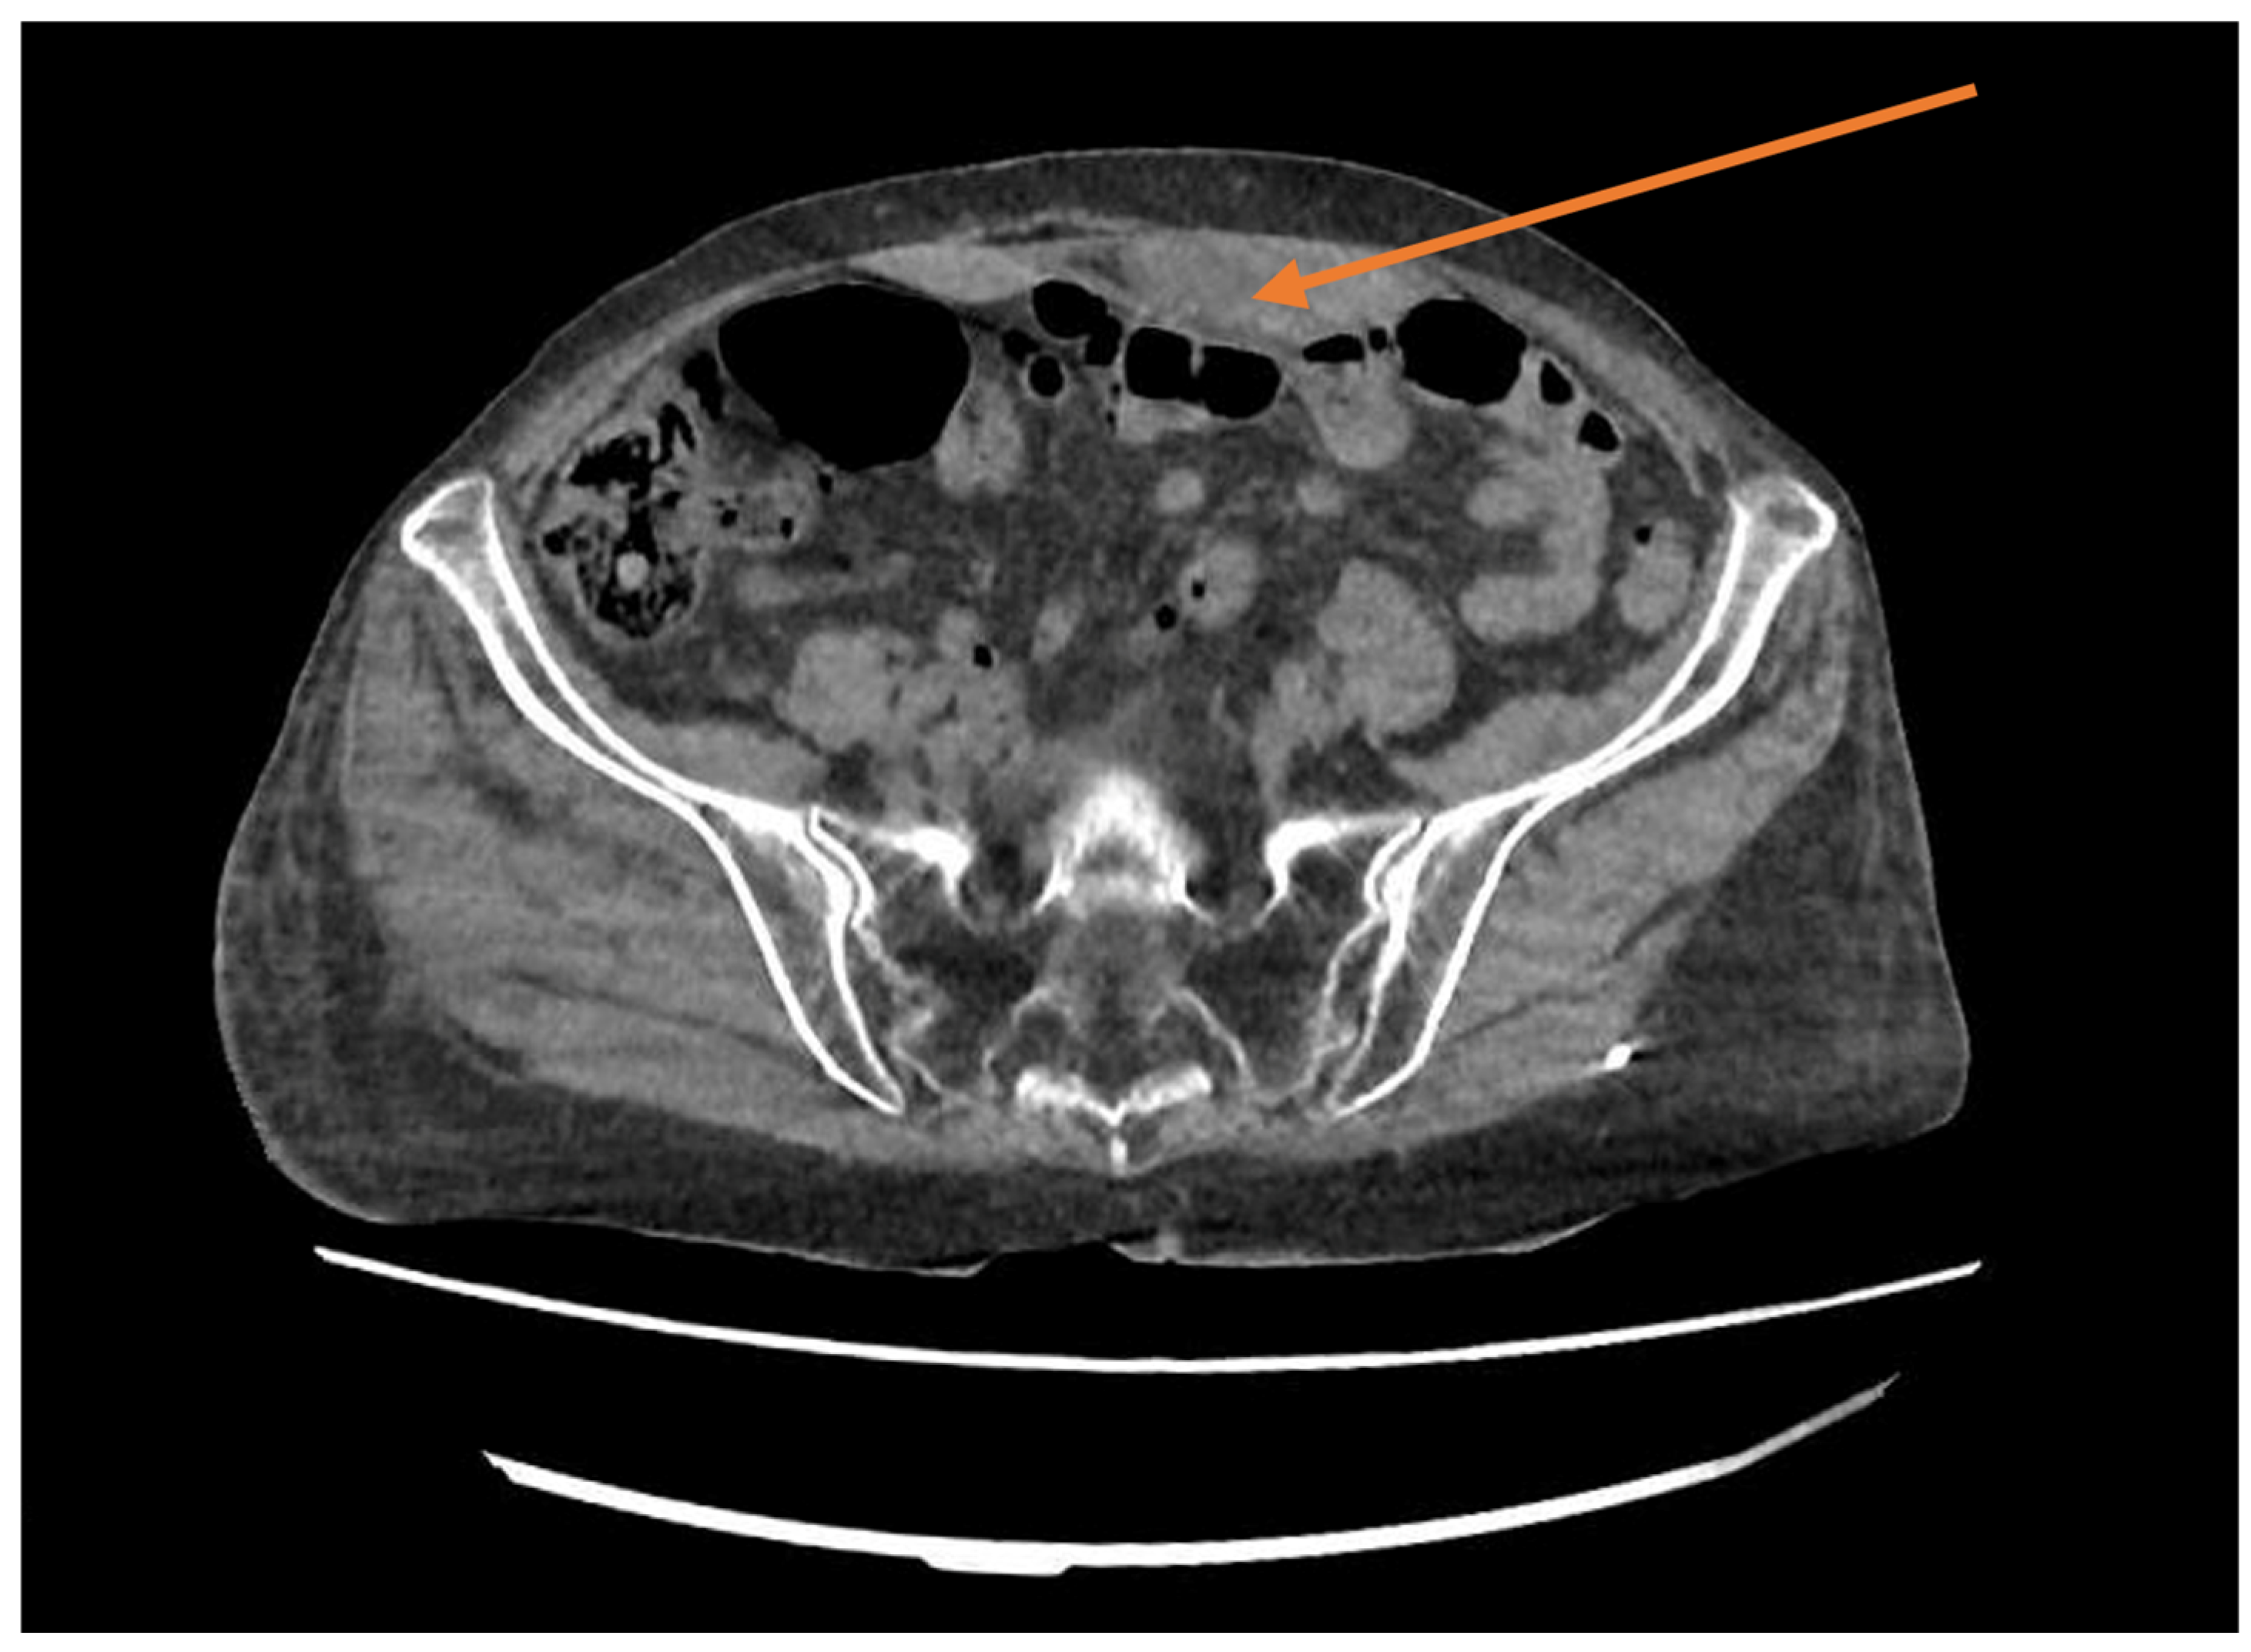

2. Case Presentation